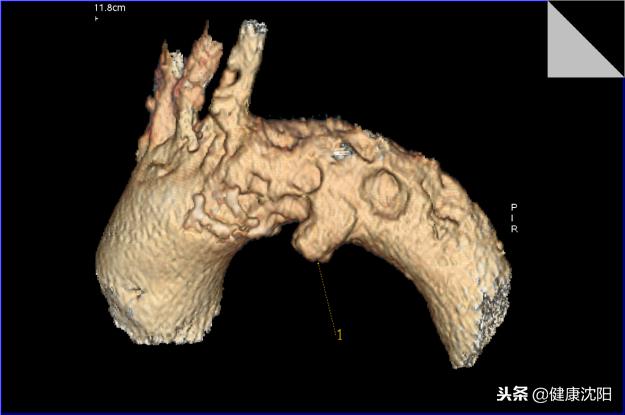

VR三维显示可以直观显示血管的大体形态、解剖,可以对病变进行明确的定位、定性诊断,可以直观地显示血管狭窄、血管瘤、动静脉畸形等病变,还可以间接判断血管壁的病变,进而提供进一步检查的必要性。CTA检查的VR技术实现了无创检查就能了解自己血管形态的目的。

显示主动脉及分支血管的形态,间接地判断血管壁的病变